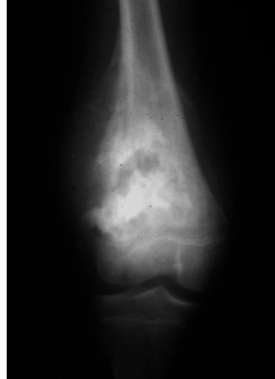

Chondrosarcoma

Imagining: medullary calcifications, cortical erosion/destruction, “popcorn”

What is this?

More cellular/pleomorphic nuceli than enchondromas

Myoxid changed matrix